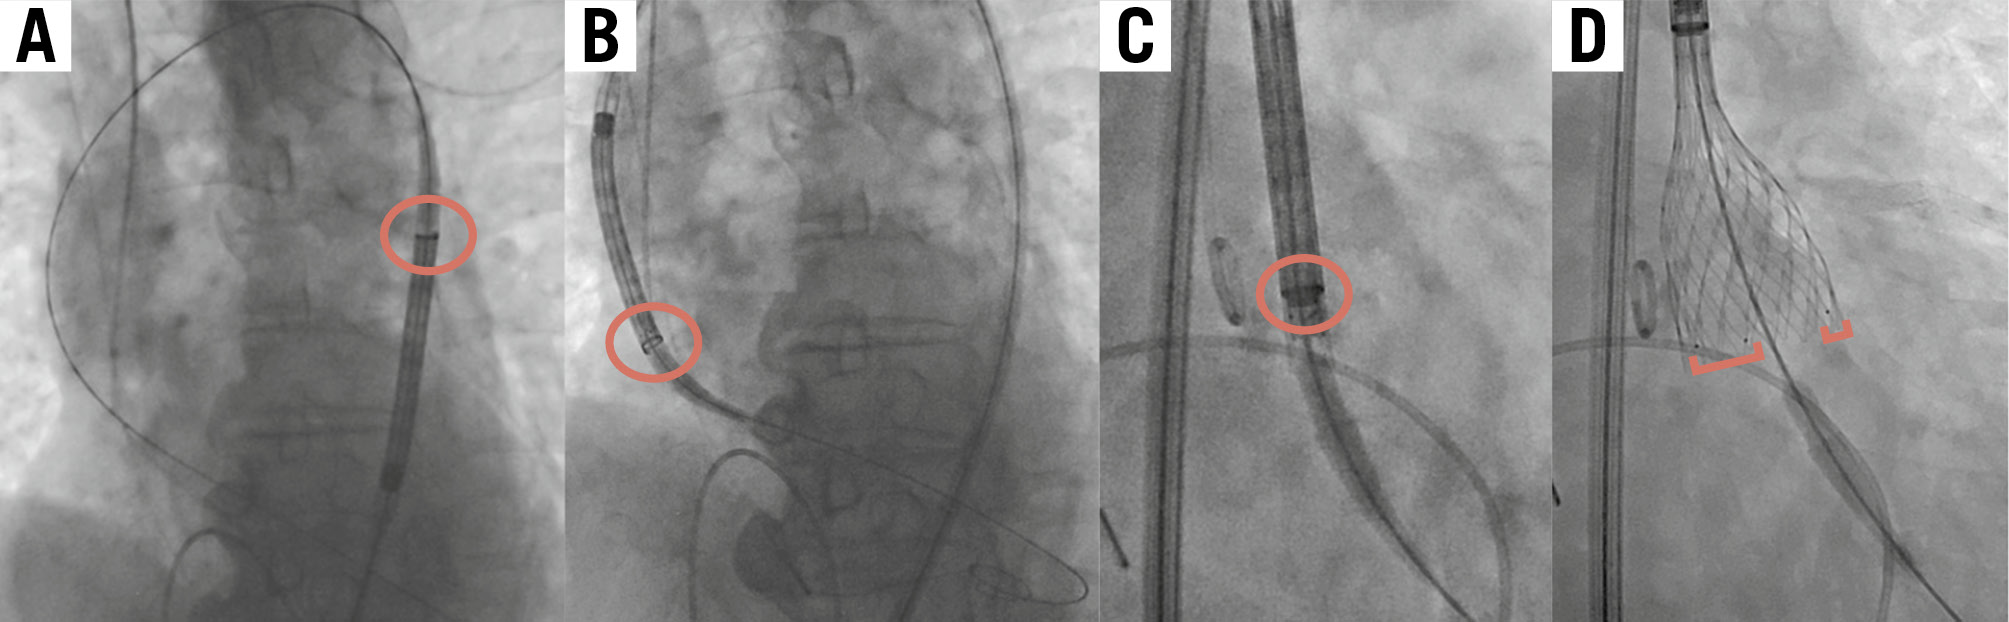

All enrolled patients underwent transfemoral TAVI using the Medtronic Evolut FX system. Prosthesis size and access site were decided by the local Heart Team based on the findings of preprocedural echocardiography and multidetector CT images. Detailed TAVI procedures have been previously described8. All the procedures followed the current best practice (Figure 1): an Evolut FX was inserted with the flush port of the delivery catheter positioned at 3 o’clock, and the position of the hat marker was assessed at the descending aorta. If the hat marker was not located at the outer curve of the descending aorta in the left anterior oblique (LAO) projection, the delivery system was rotated counterclockwise to achieve the optimal orientation (Figure 1A). The position of the hat marker was again assessed at the ascending aorta, to determine whether it remained at the outer curve (Figure 1B). Finally, valve orientation was confirmed in the cusp-overlap view and implanted in the same projection (Figure 1C). Commissural alignment on fluoroscopy was defined as 1 marker at the left-right commissure (right side) and 2 markers towards the non-coronary cusp (left side) of the annulus in the cusp-overlap view (Figure 1D). Immediately after valve implantation, CC of both the LCA and RCA was attempted via either a femoral or radial approach. Judkins left (JL) 3.5 and Judkins right 4 diagnostic catheters were used as default catheters to engage the LCA and RCA, but different types of diagnostic catheters were chosen per the operators’ discretion if the initial catheters were deemed inadequate9. Coronary guidewires or guide extension catheters were not allowed to be used for coronary cannulation.

Figure 1. Steps of transfemoral TAVI using the Evolut FX. This figure shows the key steps of transfemoral TAVI using the cusp-overlap technique. The red circles show the hat marker; the red brackets show the golden markers. A) The hat marker faces the outer curve of the descending aorta in the LAO projection. B) The hat marker faces the outer curve of the ascending aorta in the LAO projection. C) The hat marker faces “centre front” in the cusp-overlap view. D) One marker is at the left-right commissure (right side) and two markers are towards the non-coronary cusp (left side) of the annulus in the cusp-overlap view. LAO: left anterior oblique; TAVI: transcatheter aortic valve implantation